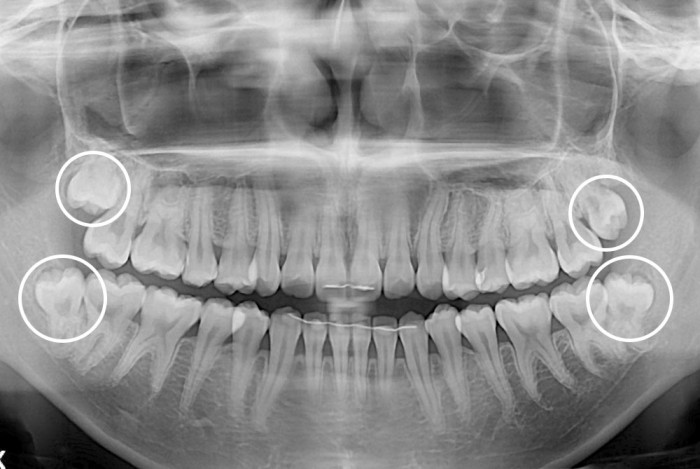

[사랑니] 사랑니

치료전 : 2019-07-09